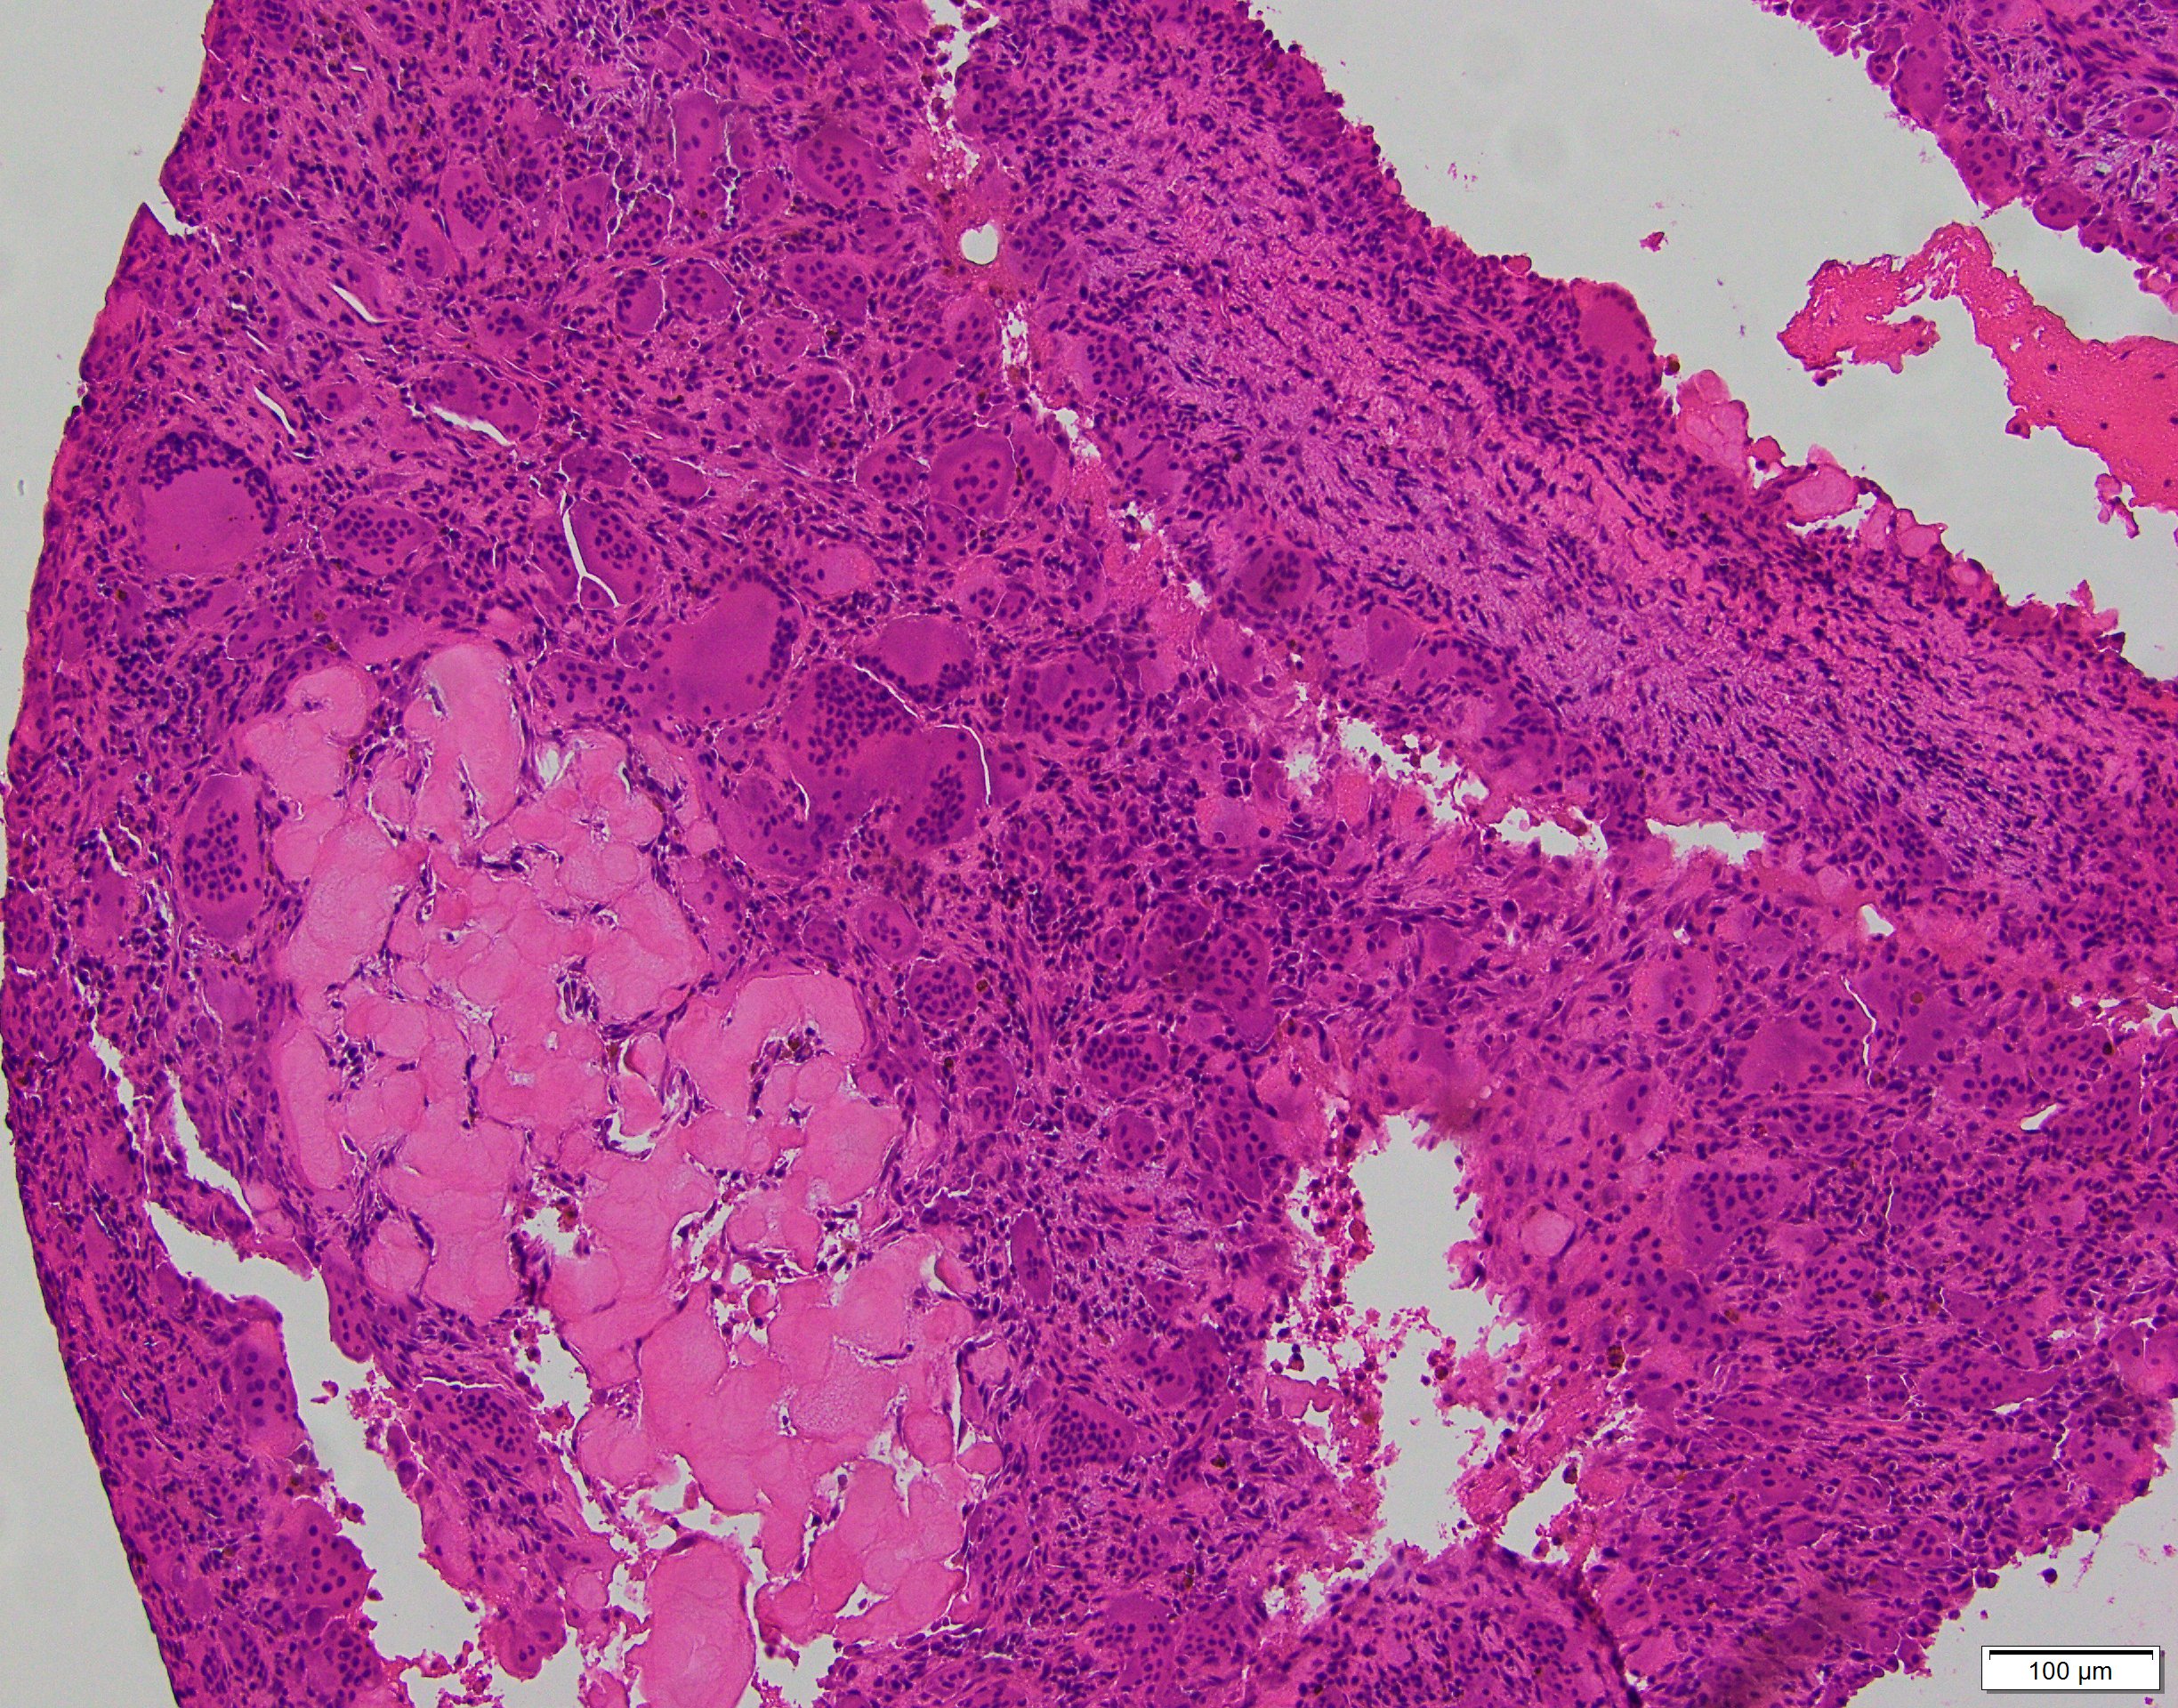

- Multiloculated cystic lesion

- Blood filled cystic spaces separated by cellular septa containing fibroblasts, giant cells and woven bone

- Calcified, basophilic material (blue reticulated chondroid-like material)

- Necrosis not common but mitotic activity is easily identified

- No cytologic atypia (Am J Clin Pathol 2015;143:823)

- Numerous giant cells in connective tissue that line large sinusoidal spaces

Microscopic (histologic) images

Contributed by Elham Nasri, M.D. and Kelly Magliocca, D.D.S., M.P.H.

A. Aneurysmal bone cyst. The H&E shows cystic spaces with stromal giant cells. Rearrangement of USP6 gene confirms the diagnosis in the above clinical and radiographic context.